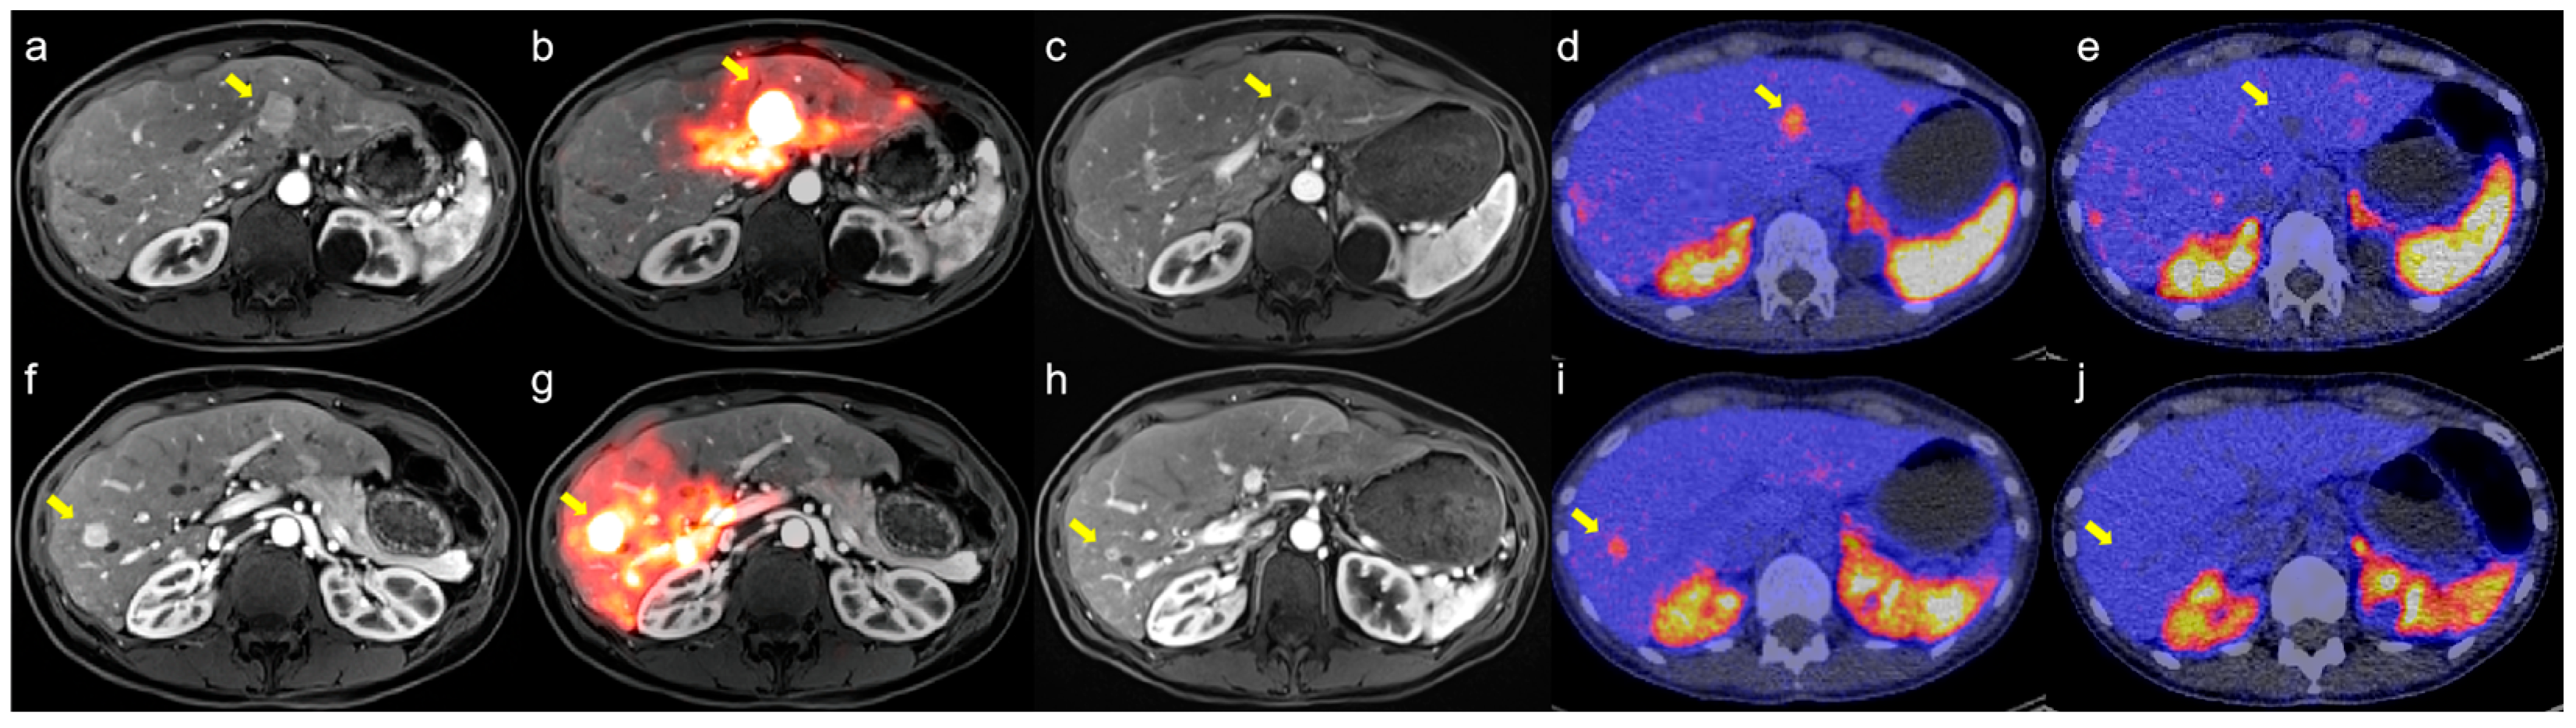

3.1.3. Clinical Outcomes

4.4. Refining Response Assessment: From RECIST to Whole-Liver Evaluation